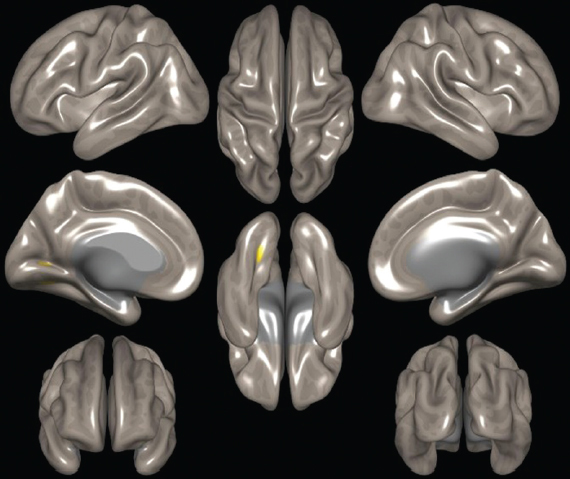

При оценке кластера № 2 (рис. 2) было выявлено увеличение активности в области язычной извилины. Данные изменения также вносят вклад в улучшение результатов клинических тестирований, а главное, в качество жизни пациентов. Увеличение в области обнаруженного кластера демонстрирует высокий потенциал к восстановлению основной нейросети покоя головного мозга, т. к. часть клеток этой области связана с медиальной префронтальной корой. Эти изменения помогают заподозрить причину положительного изменения настроения пациентов, уровня когнитивных способностей, некоторых двигательных функций.

Рис. 2. Кластер № 2 сети пассивного режима

Fig. 2. Cluster N 2 of the default mode network

Если говорить о функциональной принадлежности обнаруженных кластеров, то участки 2 и 3 кластера (рис. 2, 3), ассоциированных с сетью пассивного режима (СПР), лежат в областях, расположенных близко к структурам, участвующим в образовании данной нейросети, что свидетельствует о восстановлении функциональной коннективности самой нейросети. И на основе этого феномена потенциально можно ожидать улучшения результатов тестирований памяти, внимания, психологической составляющей, снижается выраженность двигательной дисфункции за счет улучшения функции планирования действий, повышается качество жизни.

Рис. 3. Кластер № 3 сети пассивного режима

Fig. 3. Cluster N 3 of the default mode network

Полученные нами данные о том, что в группе пациентов, которые находятся в ремиссии больше года после терапии, есть увеличение функциональной коннективности данной нейросети, свидетельствуют о появлении репаративного потенциала, возможно, на основе нейропластичности или нейроногенеза.